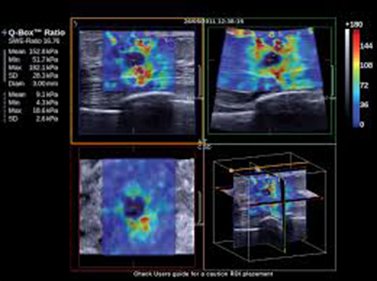

Η έγχρωμη τρισδιάστατη υπερηχογραφία (3-DPD), είναι μία αναβάθμιση του έγχρωμου Doppler, απεικονίζοντας το αγγειακό σύστημα στις τρεις διαστάσεις, με φόντο μια γκρίζα κλίμακα, που απεικονίζει μαλακούς ιστούς, δίνοντας έτσι εικόνα παρόμοια με αυτή της αγγειογραφίας, αφού επιτρέπει την άμεση απεικόνιση των πολλαπλώς αναδιπλούμενων αγγείων και τη σχέση τους με παρακείμενους ιστούς και όργανα. Με τη χρήση της τεχνικής αυτής, επιτελείται μελέτη της αρχιτεκτονικής της μικροκυκλοφορίας του όγκου και διαχωρίζονται οι όγκοι σε καλοήθεις και κακοήθεις, αφού θεωρείται ότι η ύπαρξη ακανόνιστης αγγειακής διάταξης με πολύπλοκη ή μη γεωμετρική διακλάδωση με διασκορπισμένα αγγεία συνηγορεί υπέρ κακοήθους εξεργασίας.

Η διήθηση ελέγχεται με την απεικόνιση χαρακτηριστικών ευρημάτων της αγγειογενετικής λειτουργίας, όπως νεόπλαστα αγγεία, μικροανευρύσματα και ανώμαλες διχοτομίσεις των αγγειακών κλάδων. Η διακλάδωση των αγγείων του όγκου βασίζεται στο μαθηματικό νόμο της γεωμετρικής διακλάδωσης ενός δένδρου, όπου οι μεγάλοι κλάδοι καταλήγουν σε κλάδους μικρότερου εύρους και διαμέτρου. Αν όμως συμβεί «αλλαγή» στον κυρίως αγγειακό κλάδο, τότε «αλλάζει» και η διακλάδωση, απεικονιστικό εύρημα πρώιμης κακοήθειας.

Η τεχνική (3-DPD) αποτελεί μια απαιτητική διαδικασία από μαθηματικής και τεχνολογικής απόψεως, που βασίζεται στην αλληλεπίδραση από την ανακατασκευή της γεωμετρίας των αγγείων, χρησιμοποιώντας ευκρινείς εικόνες που λαμβάνονται από μικρές περιοχές του όγκου, με αποτέλεσμα τη μέγιστη διαγνωστική ακρίβεια.

Επομένως, η χρήση του (3-DPD) επιτρέπει την εκτίμηση φυσιολογικών, παθοφυσιολογικών και αιμοδυναμικών μεταβολών στο σώμα της μήτρας, τις ωοθήκες και στους μαστούς μέσω της εκτίμησης του φαινομένου της αγγειογένεσης.